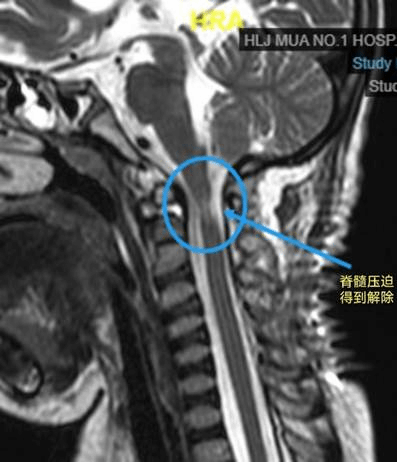

手术及时顺利的开展,术中赵伟副主任精细操作,解剖复位、重建寰枢椎稳定性。术后患儿返回ICU继续治疗,经近一个月的术后康复治疗,患儿完全恢复自主呼吸,四肢肌力也有了一定程度的恢复。

术后磁共振,脊髓压迫得到解除术后颈椎CT矢状位寰枢椎解剖复位